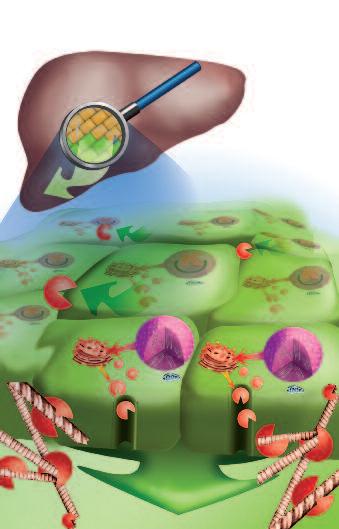

Le collagenasi, gli enzimi che digeriscono il collagene, sono prodotte da tutte le forme di cancro, indipendentemente dalla loro origine. L’illustrazione delle pagine a fianco mostra un esempio di questo processo: lo sviluppo del cancro al fegato.

Il fegato è l’organo centrale del metabolismo del corpo e, tra gli altri, è responsabile della neutralizzazione e della eliminazione delle tossine dal corpo. Tossine quali pesticidi, conservanti e molte droghe sintetiche farmaceutiche, sono le cause più comuni del cancro al fegato. Le cellule del fegato esposte a queste sostanze tossiche possono essere danneggiate o distrutte in modo permanente. La forma più frequente di danni porta ad una falsa ‘programmazione’ del materiale genetico della cellula (DNA).

Tale alterazione maligna del software della cellula segna l’inizio del processo tumorale attivando una serie di azioni biologiche che alla fine porta al cancro vero e proprio. Alcune di queste azioni sono essenziali per la crescita e la diffusione del cancro:

1. Moltiplicazione incontrollata delle cellule. Il software di una cellula tumorale è alterato in modo tale da rendere ‘immortale’ questa cella e farla moltiplicare all’infinito.

2 La produzione di massa di enzimi che dissolvono il collagene Il secondo presupposto del cancro è la produzione di enzimi che distruggono il tessuto connettivo circostante che, altrimenti, manterrebbe il tumore confinato.

Più enzimi che digeri scon o col lagene p rodu ce una cellula tumoral e, più aggressivo è il cancro e più velocemen te si diffon de attraverso il corp o, e più breve di venta l'asp ettativa di vita del paziente, semp re se tale meccan ismo non viene arrestat o.

Tumore al fegato

Cellule epatiche:

• Cellule sane (marroni)

• Cellule tumorali (verdi)

Le cellule tumorali presentano il software del nucleo alterato, questa modifica non prevede l’apoptosi (la morte fisiologica della cellula in caso di malfunzionamento o invecchiamento)

Le cellule tumorali

• si moltiplicano e

• producono collagenasi. Entrambe le produzioni sono stimolate senza limiti

Il disegno mostra gli enzimi prodotti dalle cellule tumorali epatiche che si fanno strada per espandersi.

La produzione di enzimi che digeriscono il collagene è il denominatore comune di ogni specie di tumore per crescere ed espandersi – è indifferente in quale organo la malattia compare.